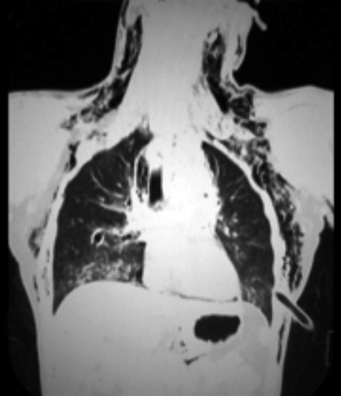

La tomografía computada de cuello y tórax mostró evidencia de neumotórax residual derecho de menos del 10% y neumotórax izquierdo resuelto. También hubo la presencia de un pequeño hematoma al nivel del tronco supraaórtico del lado izquierdo con neumomediastino (superior) (figuras 4 y 5).